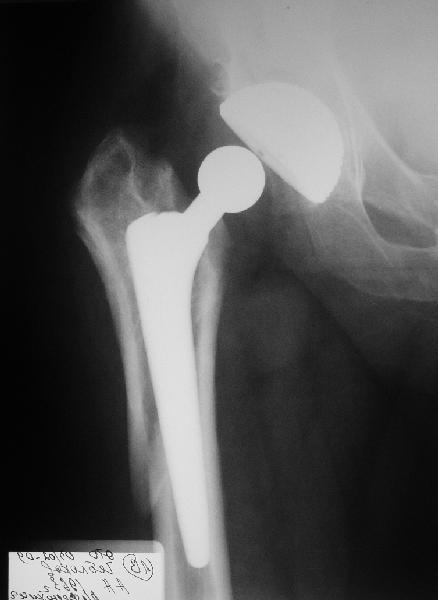

Перипротезный перелом бедра

Мужчине 1963 г.р. в октябре прошлого года в Кургане сделано эндопротезирование правого тазобедренного сустава (последствия перелома шейки бедра) бесцементным протезом Cerafit.

Все было благополучно, пациент уже ходил без трости, когда в начале января 2009 упал на улице на правый бок.

Госпиталирован по месту жительства (МСЧ г. Новоуральск). Уложен на скелетное вытяжение. На снимках от 3 февраля видно миграцию ножки в дистальном направлении, она явно нестабильна. В нашей больнице вряд ли что-то удастся сделать. Сопутствующих заболеваний нет. Хотелось бы получить совет по тактике. Если нужно ревизионное протезирование, куда лучше пациента направить? Спасибо.

У пациента перипротезный перелом бедра тип 2Б по ванкуверской классификации.

Показано ревизионное протезирование с заменой ножки. Вероятно в Курган. Можем принять на лечение, но при наличии источников финансирования - дорого.